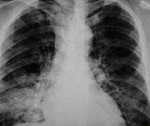

При нодулярной форме рака на рентгенограммах и КТ легких определяют одно или несколько округлых периферических образований неоднородной структуры с бугристыми контурами, расходящимися в стороны линейными связками. Для пневмоноподобной формы характерно слияние очагов в единый гомогенный инфильтрат. Распространенный вариант проявляется наличием множества различных очагов или признаков повреждения легочной интерстиции.

Бронхоальвеолярный рак часто возникает в виде других респираторных заболеваний. Прежде всего, его следует отличать от пневмонии, туберкулеза и легочного саркоидоза. При отсутствии положительной рентгенологической динамики или появлении новых вспышек на фоне лечения вышеуказанных патологий антибактериальными или туберкулезными препаратами следует провести комплексное обследование пациента для исключения инвазивной аденокарциномы.